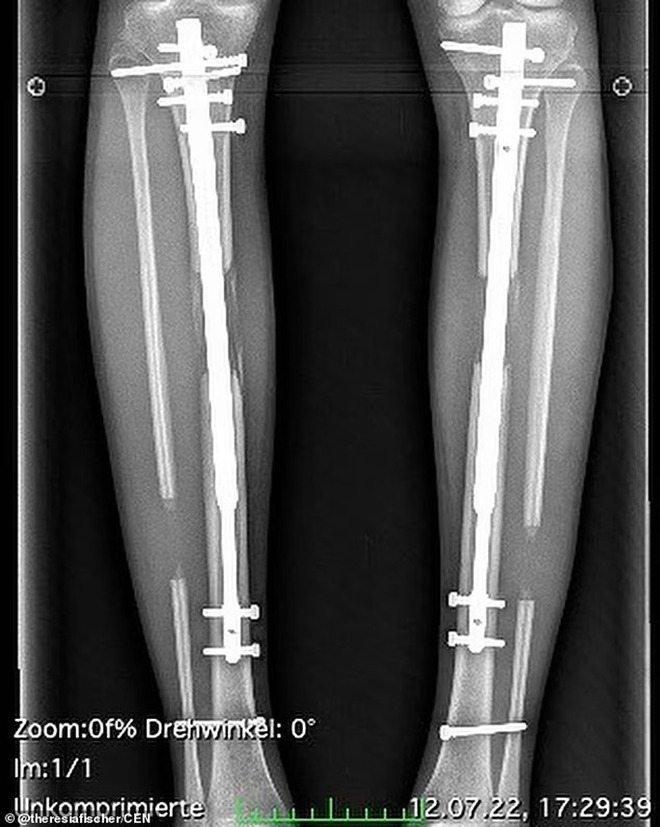

Cô thực hiện hai cuộc phẫu thuật kéo dài xương chân

Sau đó, cô trải qua một cuộc phẫu thuật tiếp theo vào tháng 3-2022 để kéo chân dài thêm hơn 5cm. Chi phí cả hai lần phẫu thuật hơn 128.000 bảng Anh.